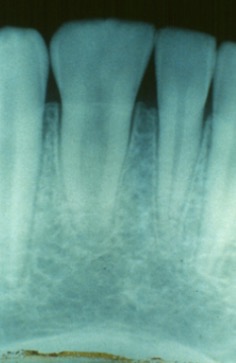

Dentinogenesis imperfecta

-calcified pulp chambers; bell shaped teeth; this is a hereditary disorder.

-This condition is sometimes correlated with osteogenesis imperfecta